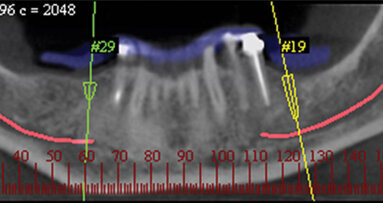

At the time of re-entry, the patient’s blood pressure was 113/69 with a heart rate of 64 (Figs. 4, 5). Under local anesthetic (Lidocaine 2 percent HCl with epinephrine 1/50,000 x 2 cpl), a tissue punch access was done using a 3.8 tissue punch XiVE drill (DENTSPLY Friadent).

The pilot drill from the ANKYLOS implant system (DENTSPLY Friadent) was then used to drill 6 mm, just short of the sinus floor (Fig. 6). A series of XiVE osteotomes, from size 2.0 up to 3.4, were used to perform a sinus lift using the Summer’s technique. The osteotomy was prepared to a depth of 11 mm (Fig. 7).